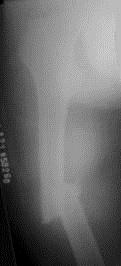

病历摘要: 患者×××,男性,34岁,车祸致伤右大腿后肿胀、疼痛、畸形,活动受限2小时。查体:右大腿肿胀,成角畸形,骨连续性中断,右足背动脉搏动存在,右足...

问题 病历摘要: 患者×××,男性,34岁,车祸致伤右大腿后肿胀、疼痛、畸形,活动受限2小时。查体:右大腿肿胀,成角畸形,骨连续性中断,右足背动脉搏动存在,右足伸屈功能正常。 股骨骨折并发症有哪些?

选项 A、骨髓炎 B、骨折不连接 C、膝关节活动障碍 D、骨折畸形愈合 E、坐骨神经损伤 F、股神经损伤 G、股动脉损伤 H、股静脉损伤

答案 ABCDEGH